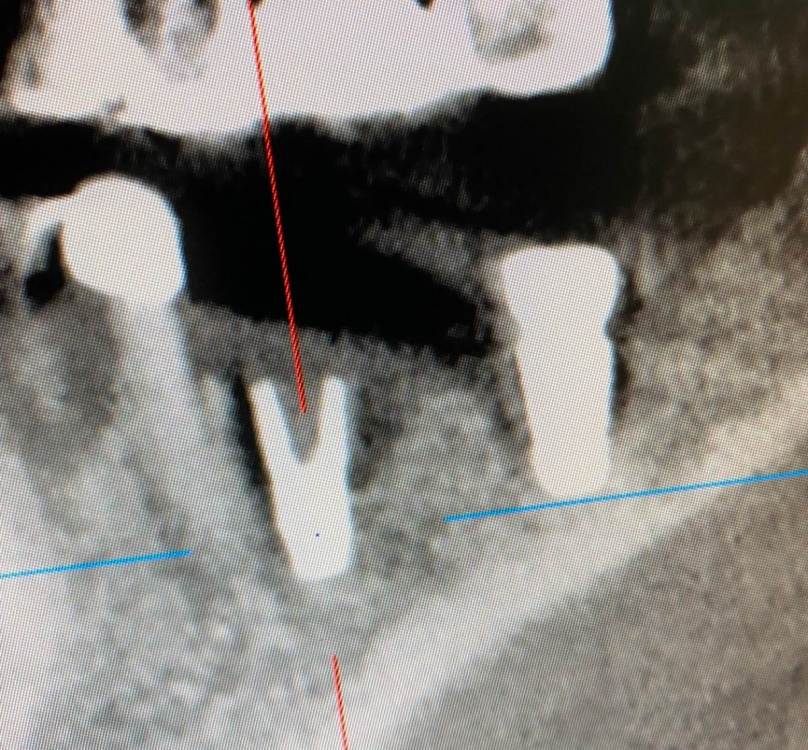

колесников Опубликовано 6 июля, 2022 Поделиться Опубликовано 6 июля, 2022 Здравствуйте коллеги! Впервые вижу перелом Астры. Впервые получил перелом «своей»Астры. Вероятно ещё никто не видел перелом Астры профайл. Диаметры 4.5 и 5.0. Самое неприятное что это произошло за 1,5 года. Ошибка протезирования. Перегруз. Резорбция. Фрактура. Из интересного. Одновременно с имплантацией была произведена контурная пластика поднадкостнично,графт шурос. Это работает. Ставим галочки и двигаемся дальше. 2 1 1 Ссылка на комментарий

TIGER Опубликовано 11 июля, 2022 Поделиться Опубликовано 11 июля, 2022 тут ожидаемо,недозаглуб,grade4 конус ....и закономерный финал,иесли там винтовая с уровня имплантов то вообще картина маслом Ссылка на комментарий

Irouil Опубликовано 11 июля, 2022 Поделиться Опубликовано 11 июля, 2022 (изменено) Не понял - почему недозаглубен? Оба винтыа где-то на 1мм под краем гребня Изменено 11 июля, 2022 пользователем Irouil Ссылка на комментарий

TIGER Опубликовано 11 июля, 2022 Поделиться Опубликовано 11 июля, 2022 @Irouil первое фото Ссылка на комментарий

Irouil Опубликовано 11 июля, 2022 Поделиться Опубликовано 11 июля, 2022 (изменено) По фото невозможно понять что там было заглубленно и что нет, на рентгене картина объективнее Я вижу из возможных косяков пл хирургии только избыточно лингвальное позиционирование платформы у одного из винтов, из-за чего стенка очень тонкая - если там случилась резорбция, то иллюзию недозаглубения на фото она вполне может создать К тому же, ТС раньше рассказывал что часто идёт на тунельную твердотканную аугментацию при имплантации в таких случаях, если тут тоже - то для меня неточное позиционирование объясняется именно тунельным подходом и ограниченным обзором по такому поводу. Это, в сущности, единственное, что останавливает меня самого попробовать подобную аугментацию как альтернативу минисосиджу. Но надо услышать ТС, это только мои догадки Изменено 11 июля, 2022 пользователем Irouil Ссылка на комментарий

TIGER Опубликовано 11 июля, 2022 Поделиться Опубликовано 11 июля, 2022 @Irouil ну тут много ума не надо и трёхмёрной информации,чтобы понять исходя из этого фото,что там изначальный недозаглуб был (платформа торчит на уровне десневого края),плюс фактор протетики возможно сыграл....? Ссылка на комментарий

Irouil Опубликовано 11 июля, 2022 Поделиться Опубликовано 11 июля, 2022 @TIGER ладно, давайте подождём мнения Игоря, на рентгене (который был ДО резорбции и явно объективнее, чем фото ПОСЛЕ неё, да ещё и не в академической проекции) я явного недозаглубения не вижу, хотя глубить, вроде бы, ещё было куда и тут вопрос скорее в том, почему ТС не решил перестраховаться 1 Ссылка на комментарий

Astronaft Опубликовано 12 июля, 2022 Поделиться Опубликовано 12 июля, 2022 (изменено) 06.07.2022 в 14:28, колесников сказал: Протокол отработан как автомат Калашникова,платформа относительно Зенита и вершины гребня,высота уступа,наличие и ширина прикреплённой слизистой. Далее процесс запускается вспять и через два года наблюдаем прирост кости на скосе гребня. Это хорошай заговор-пожелание. В жизни часто не так. По одной простой причине общее здоровье человека влияет намного сильнее. Пародонтологический статус - если есть карманы хоть 5-6мм где-то во рту риск пери-имплантных явлений возрастает. Микробиота слюны, вязкость, диета, качество гигиены, обший воспалительный фон- это сфера влияния пациента. Качественное местное исполнение это хороший фундамент - только одна из составляющих. Астра Профаил - укороченный, асимметричый конус. 3мм с одной стороны, 2мм с другой. Конфигурация перелома закономерна - сами абатменты раскололи высокую стенку от низкой. Я бы предположил что тещины первичны, резорбция это следствие. Изменено 12 июля, 2022 пользователем Astronaft 2 4 Ссылка на комментарий